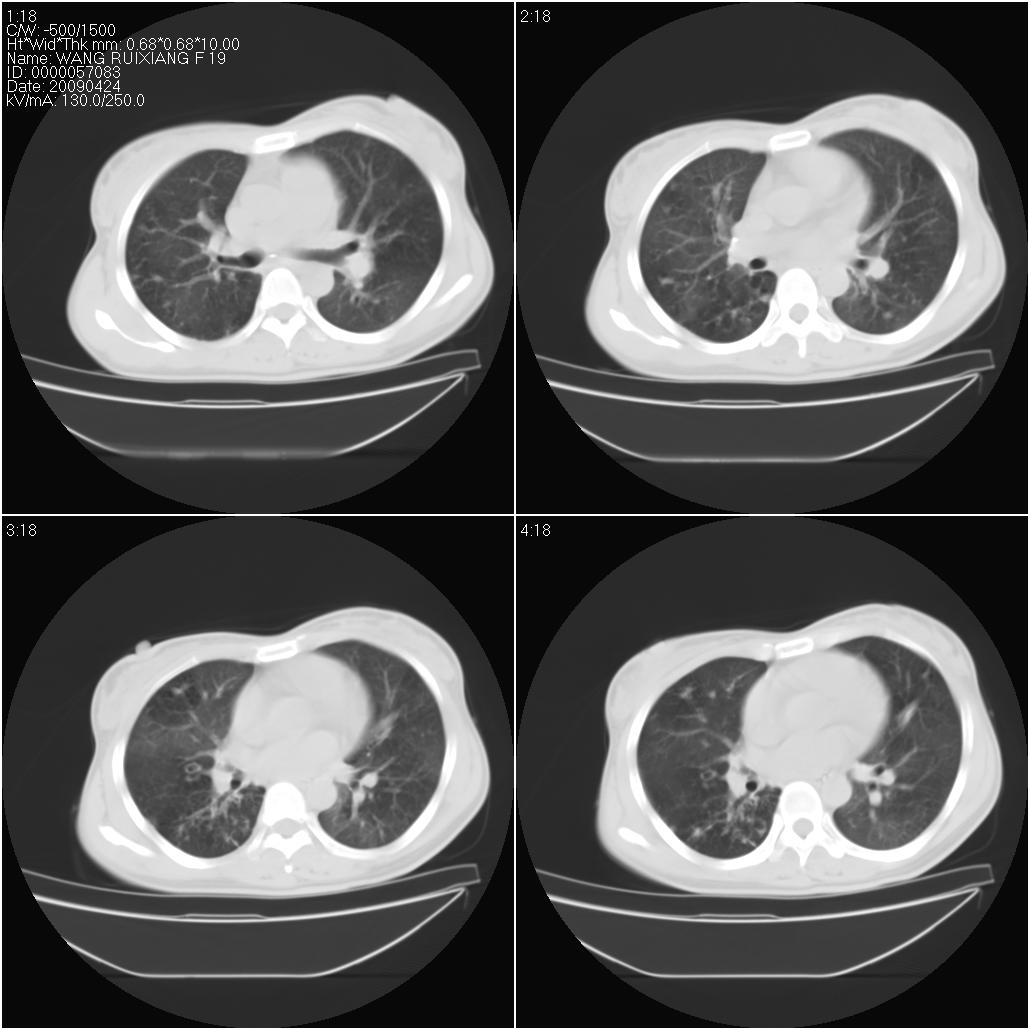

标题: CT19588:女性,39岁。患者胸闷不适,上楼时气喘。 [打印本页]

标题: CT19588:女性,39岁。患者胸闷不适,上楼时气喘。

片子上的年龄为19岁,是操作错误。该患者于去年5月份曾做平片和ct扫描,和这一次的ct检查没有明显变化。当时诊断为肺结核,进行抗痨治疗至今,但没有改善。呼吸功能试验为混合型呼吸困难。除此之外,该患者没有其他方面没有的临床症状和体征

两肺见斑点片状阴影,部分病灶密度较高,右下肺见小囊状及柱状蜂窝状阴形,考虑为两肺结核以阵旧性为主,右下肺支扩。

1)两肺继发性肺结核(以增殖病灶为主)。2)两肺下叶支气管扩张。

结合病人年龄(特别是生育期妇女)及临床表现多考虑淋巴管肌瘤病。